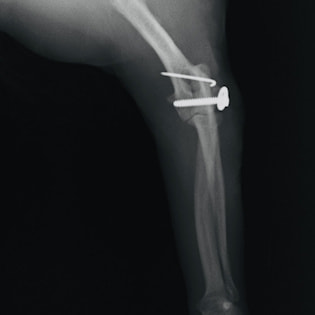

症例3:キルシュナーワイヤーのピンニングによる整復

ペルシャ猫 11ヶ月齢 雄

他院にて左大腿骨遠位の成長板骨折(salter-harrisⅠ型)が認められており、治療相談を目的として来院。当院にて、キルシュナーワイヤーを用いたピンニングにより骨折部位の整復を行いました。術後の経過は良好で、現在も経過観察中です。

術後レントゲン

Arthrex社のターゲティングデバイスを用いてピンニングの位置を調整することで、確実な固定を行っています。当院ではこの手術器具以外にも、人の手術にも使用される様々な器具を導入し、手術精度を高め、また医療メーカーと新しい器具の開発、試作にも取り組んでおります。